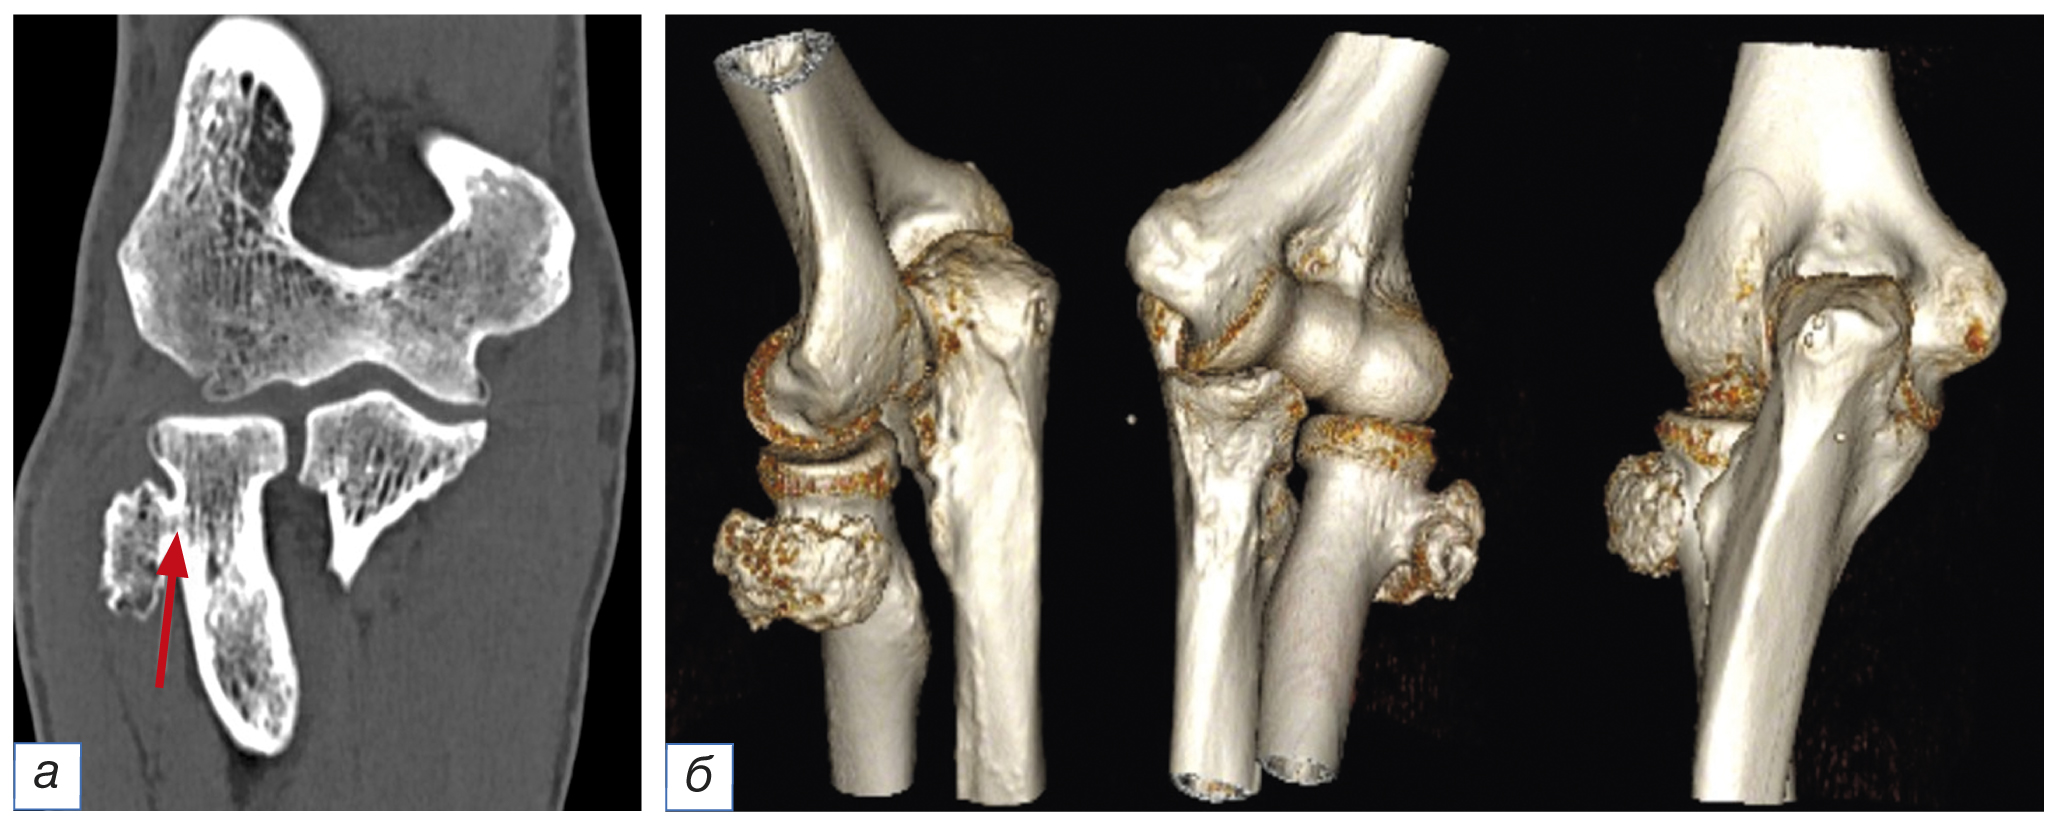

По данным КТ локтевого сустава определены расположение новообразования (по заднелатеральной поверхности шейки лучевой кости) и его размеры (19×28×31 мм) (рис. 3). С помощью КТ установлено также, что губчатая кость в составе экзостоза в области основания сообщается с губчатой костью шейки лучевой кости, что является патогномоничным признаком остеохондромы.

Рис. 3. Компьютерная томография левого локтевого сустава, фронтальная плоскость (а): стрелкой указано сообщение губчатой кости новообразования и шейки лучевой кости. 3D-реконструкция левого локтевого сустава по данным компьютерной томографии (б)

Fig. 3. Computed tomography of the left elbow joint, frontal plane (а): the arrow indicates the connection between the cancellous bone of the neoplasm and the neck of the radius. 3D reconstruction of the left elbow joint (б)